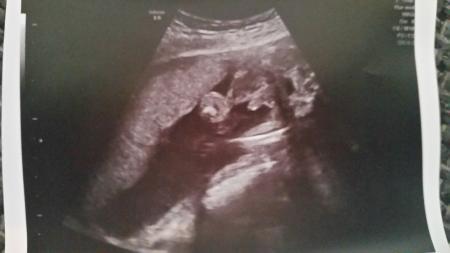

Hallo, Ich wollte euch fragen ob es sich um ein Jungen-Outing handelt oder sich die Ärztin irrte. Ich bin in der 23. Woche schwanger mit meinem ersten Baby und das USBILD wurde vor einer Woche gemacht. FÄ sagten mir dass es eindeutig ein Junge ist. Ich habe mich auch auf einen Jungen eingestellt und möchte nicht enteuscht werden. Kinderzimmer ist auch schon fertig mit Jungen-Tepeten. Meint ihr dass das Outing sicher ist? Mein Mann meint dass das was dort der Penis sein soll zu groß für so ein Baby aussieht und hat noch Hoffnung dass es ein Mädchen wird.

Bild zu Eindeutiges Jungen-Outing - Schwanger - wer noch? Rund um die Schwangerschaft

Ich habe 3 Jungs und bin mit dem 4. Jungen schwanger. Auf dem Bild sieht man definitiv den " Zipfel ". So " groß " sah es auch bei meinen Bubis aus . Da wird dein Mann beim nächsten Kind auf ne Püppi hoffen müssen

Vielen Dank für die Antworten Ich War mir nicht so sicher da eine andere Gynäkologin 2 Tage vorher auch einen Jungen gesehen hat, dann hat sie aber die Geschlechtsteile nicht mehr gefunden und meinte eher Mädchen, obwohl sie am Anfang sagte Junge und uns den Penis und Hoden zeigte. Deswegen war ich etwas irritiert und 2 tage später als meine FÄ sagte dass es ein Junge ist habe ich extra nachgefragt ob sie sich sicher wäre, 2 FÄ die dort in der Klinik arbeiten meinten ganz sicher Junge.

Sieht für mich (schwanger mit dem zweiten Buben) klar nach Junge aus und in der 22. SSW sind die Jungs auch relativ sicher. LG Lilly